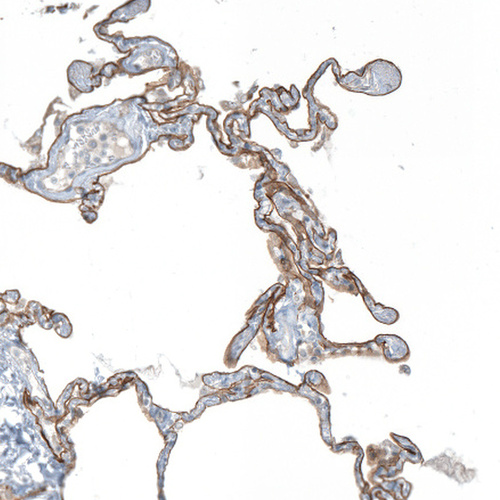

Immunohistochemical staining of human lung shows moderate membranous positivity in pneumocytes.